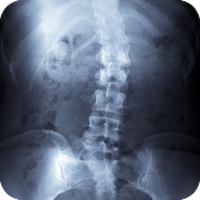

Scoliosis is a sideways curve of the spine that causes stiffness and pain. People with scoliosis have a sideways curve in their spine that makes an "S" or "C" shape.

Scoliosis is derived from the Greek term meaning curvature. People with scoliosis have a sideways curve in their spine that makes an "S" or "C" shape. The vertebrae can rotate at the thoracic level of the spine causing this curve and resulting in a hump near the rib cage. If the curve is more than 60 degrees it is considered serious. Usually this curve makes the waist or shoulders uneven. And unlike the normal curvature of the spine, adjusting your posture will not correct the problem.